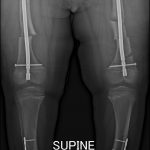

MULTITRAUMA AFTER MOTOR VEHICLE ACCIDENTS

Unfortunately I often see broken bodies after motor vehicle accidents. The injuries sustained are often lifechanging and though the science of orthopedics is advanced, not everything can be repaired to perfection.

Avoiding driving at night and after a drink seem to be the best ways to avoid accidents. Accidents are also more prone to happen on wet roads.

Shown here are the x-rays of a young patient who drove at night after taking a few drinks. The fractures are all open and this will be a life changing event for him.